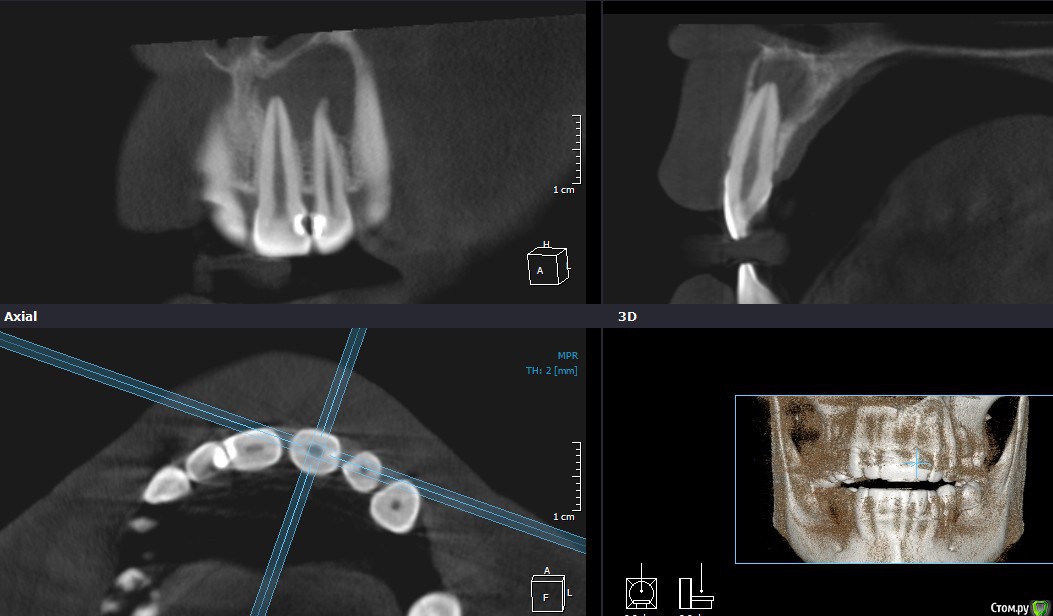

Рустам Опубликовано 17 января, 2016 Поделиться Опубликовано 17 января, 2016 Добрый вечер коллеги! Обратилась пациентка с жалобами на наличие свища в области 22 зуба. Сделали КТ, обширный очаг в области 21, 22. Как считаете, можно попытаться в данной ситуации обойтись консервативным лечением, без хирургии? Ссылка на комментарий

DmitrySH Опубликовано 17 января, 2016 Поделиться Опубликовано 17 января, 2016 Вот честно не вижу заочной необходимости в МТА или IRM. Первичное эндо, констрикция сохранена. И декомпрессия уже самостоятельно наладилась.Я за эндо через кальций до периода стойкой ремиссии. Далее уже закрывать, апексфикация и декомпрессия уже входе лечения по мере необходимости 8 Ссылка на комментарий

Л Ю С Я Опубликовано 18 января, 2016 Поделиться Опубликовано 18 января, 2016 Вот честно не вижу заочной необходимости в МТА или IRM. Первичное эндо, констрикция сохранена. И декомпрессия уже самостоятельно наладилась.Я за эндо через кальций до периода стойкой ремиссии. Далее уже закрывать, апексфикация и декомпрессия уже входе лечения по мере необходимости+1, только выясните витальность 2.1. Судя по кт он уже дохлый. Но не факт Ссылка на комментарий

Ico Опубликовано 18 января, 2016 Поделиться Опубликовано 18 января, 2016 Поговорим о экономической точке зрения , если получили провал на кальции , вы применяете IRM для чего ? Вы уже получили провал от кальция , МО выжило после кальция,а может и произошла адаптация к нему , чего вы добиваетесь при IRM (Ваша цитата "нужны хорошие условия,где нет вне канальной инфекции"). О сроках кальция не упоминаем. "есть результаты с IRMом" - хорошо, а допускаете ли вы что клинический случай тот же? Или же у вас внеканальной инфекции просто уже не было в Вашем случае ? Разобраться не могу, в этом протоколе для бабосиков ? Ок)) на терапии сложно "бабосиков" заработать))) тут нужен талант ,особенно на IRMе.Под провалом на кальции я понимаю,что недообработал апекс и постепенно увеличиваю его диаметр на 2-3 размера каждый раз до белой стружки,усложняю протокол ирригации и активации.Это занимает 2-3 посещения с интервалом 2 недели.Затем,когда из канала перестает литься,либо закрывается свищевой ход я оцениваю чем паковать и очень часто это апексы уже не 40 - 45 - 50 а 60 - 80 - 100 как правило после второго посещения я принимаю решение как вести пациента дальше,один из вариантов я описАл в посте номер 3.В данном кейсе DmitrySH правильно подметил,что констрикция сохранена и есть хороший шанс обработать и запаковать канал стандартно,получив хороший клинический результат.inSight,коллега обратите внимание,что это эстетически значимая зона,где после удаления будет очень дорого восстановить функцию и эстетику,а вырастить качественную кость может только эндодонтист. Ссылка на комментарий